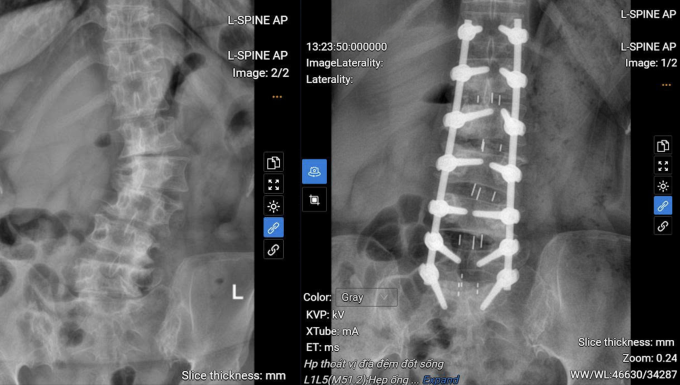

Trong quá trình phẫu thuật kéo dài 5 giờ, bác sĩ Duận đã sử dụng hệ thống C-arm để định vị chính xác vị trí bắt vít, giảm thiểu nguy cơ tổn thương thần kinh và rút ngắn thời gian phẫu thuật. Phương pháp này giúp giảm mất máu và hạn chế xâm lấn, tạo điều kiện cho bệnh nhân phục hồi nhanh hơn. Tổng cộng 14 vít đã được sử dụng để cố định và nắn chỉnh cột sống của bà Pha. Bác sĩ Duận đã loại bỏ các cấu trúc gây chèn ép, mở rộng ống sống để giải phóng tủy và các rễ thần kinh, đồng thời loại bỏ các phần đĩa đệm thoát vị và gai xương. Đĩa đệm được thay thế để hàn khớp liên thân đốt sống, đảm bảo độ vững chắc cho cột sống.